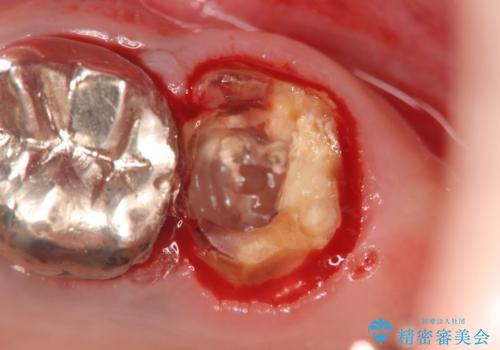

X線検査の結果、左上6には歯根破折、左上7には銀歯の下に大きな虫歯の再発が認められ共に抜歯をせずには症状の改善が見込めない状況です。

奥歯を2本失ったのち、しっかりと噛める環境へと整備するため、しっかりと骨の造成を行い清掃性を高めたインプラント治療を行っていくこととしました。